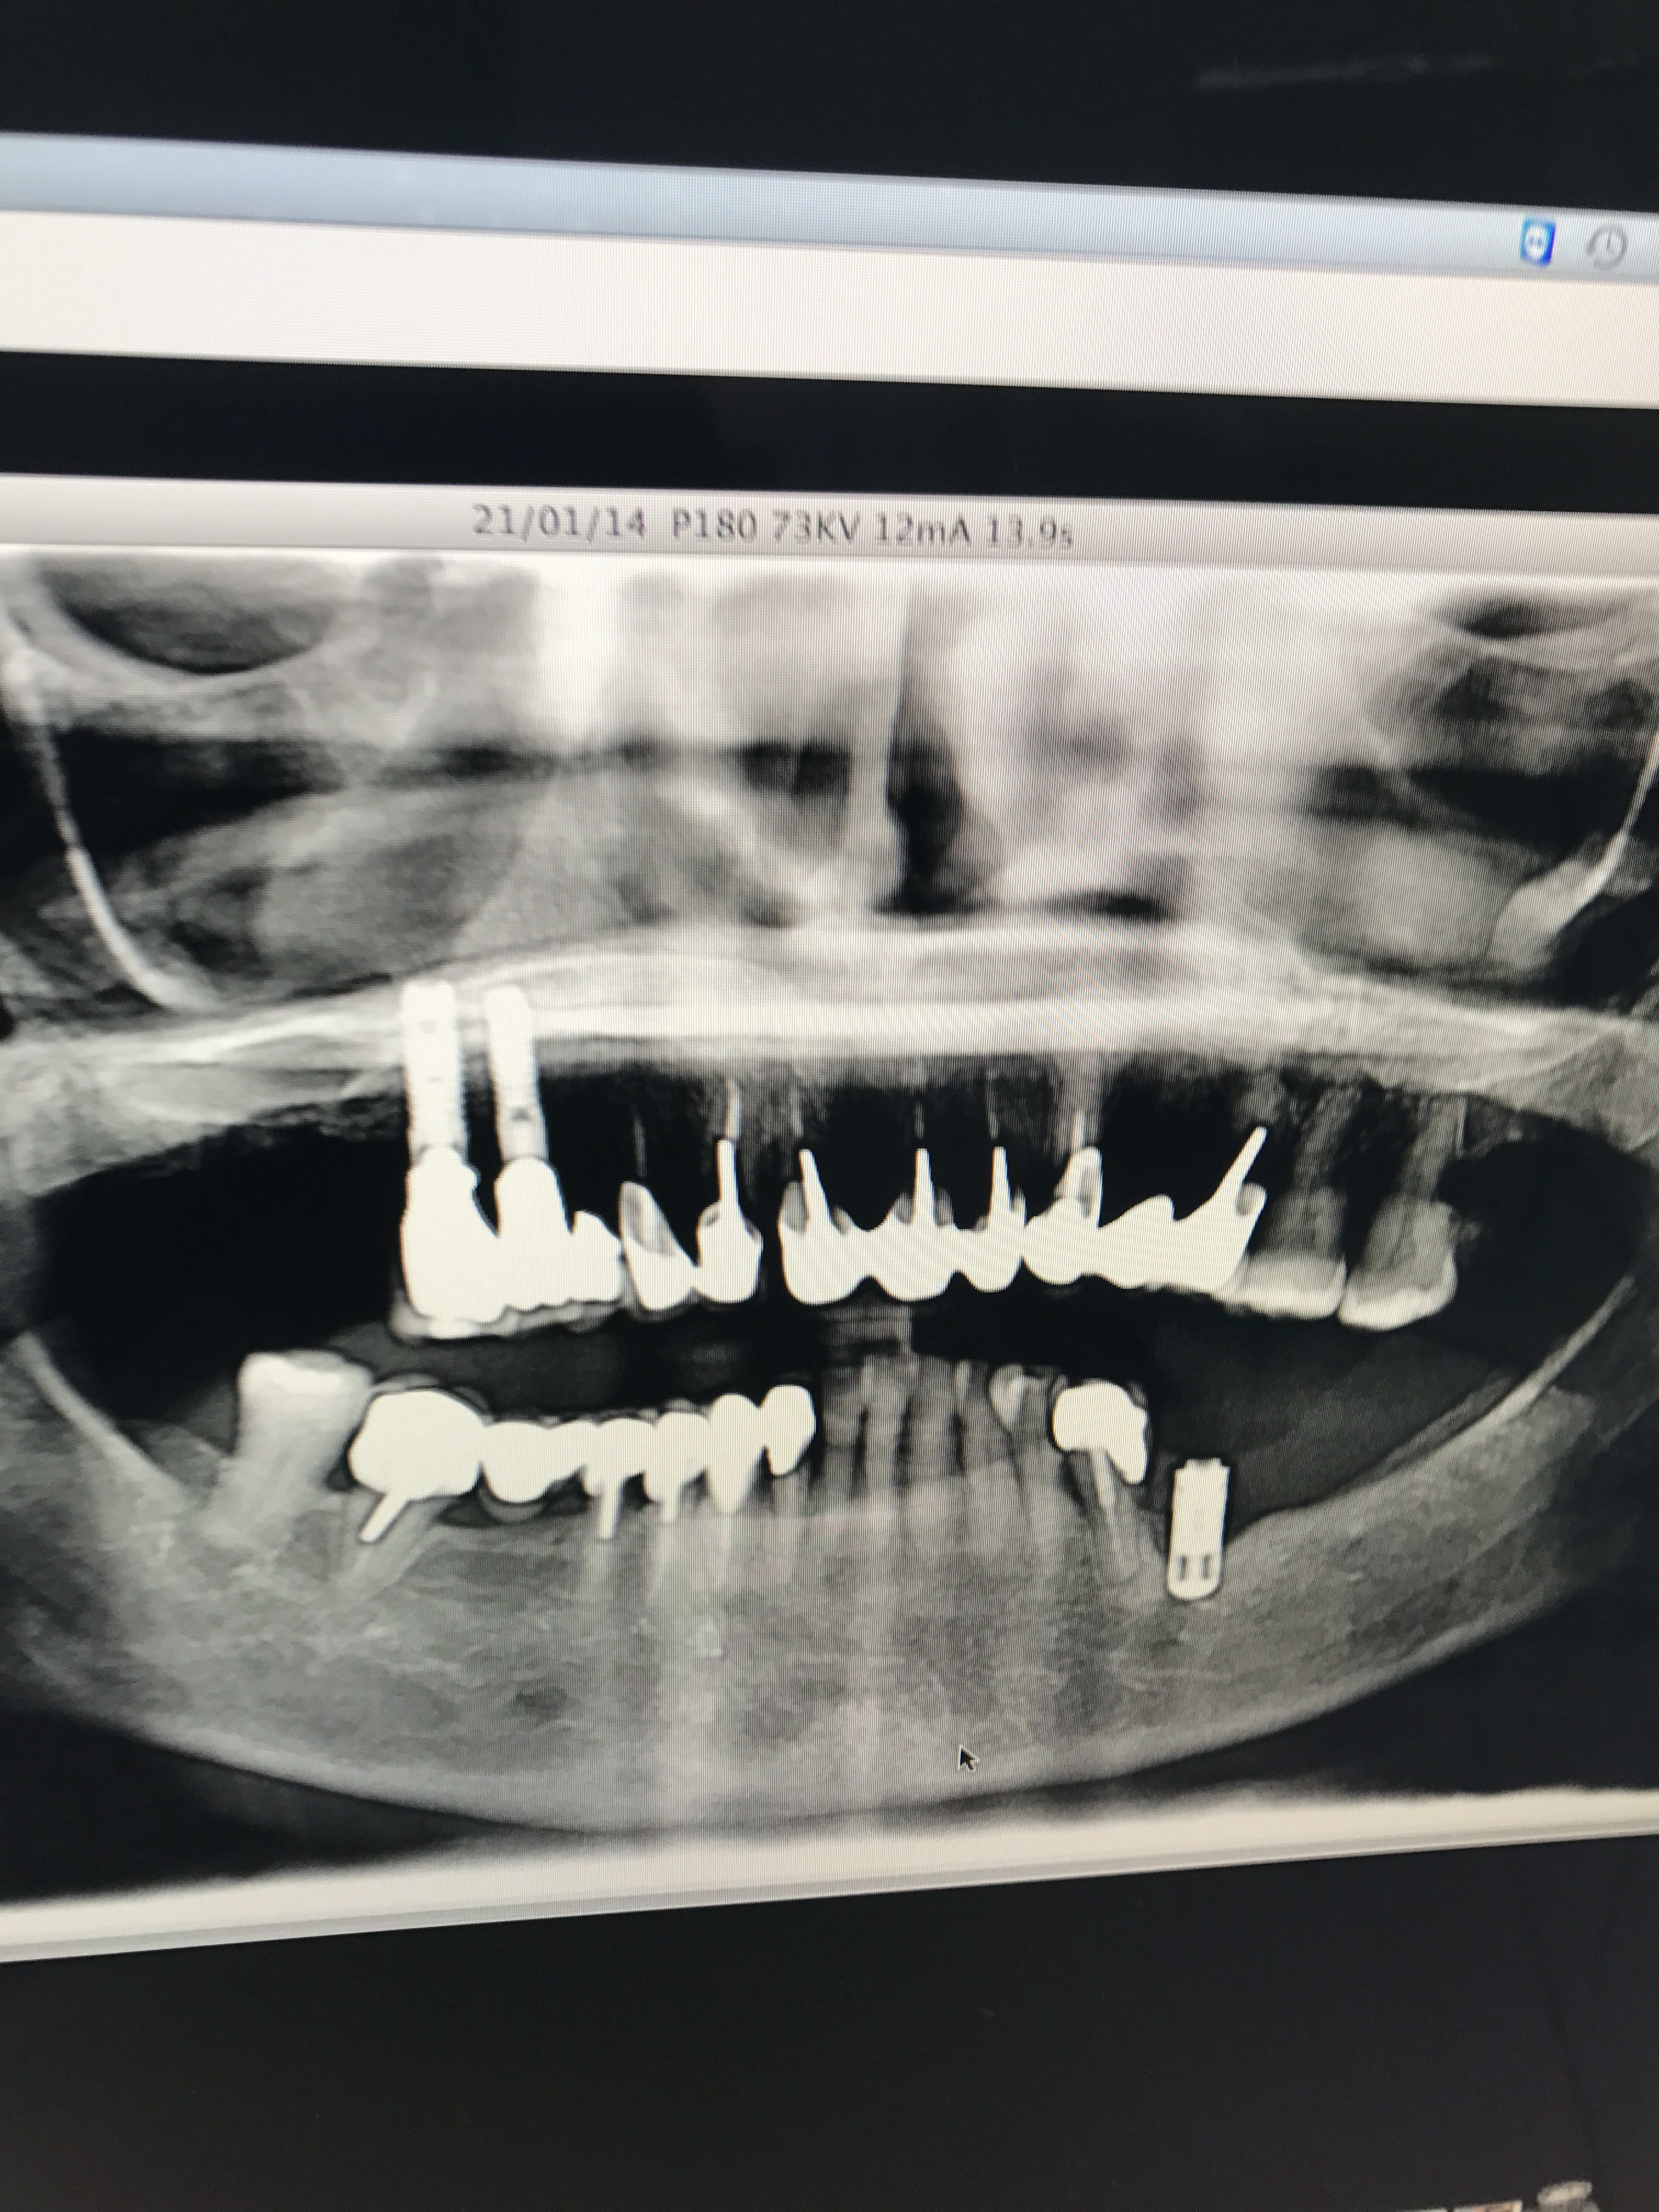

et voila messieurs !

serf EVL donc connexion à plat...ce qui veut dire multiunits inutiles si tu n'utilises pas l'hexagone (ce qui est le cas déjà ici si tu étudies bien la rétroalvéolaire)

mais!: l'implant le plus mésial n'est pas dans un axe idéal ce qui veut dire que l'émergence de la vis sera merdique à gérer si tu veux faire de la transvissée...

tu n'as pas d'autre choix que de refaire de la scellée pour ce cas...et petit conseil, utilise des piliers indexés et non pas des piliers sans indexation comme ici...

amha çà c'est dévissé car les piliers n'ont pas étés mis dans la bonne position, ils ont été vissés/serrés de travers...la mastication les a fait revenir dans la bonne position...mais du coup ils ne sont plus serrés...

P.S: le vieil IMZ est bon pour le haricot...

PS: En 35-34 c'est l'exemple même de ce qui arrive dans un os D1. Certains appeleraient ça une peri implantite. .. à tort à mon avis. Il faut rétablir la vascularisation sinon re échec 🤔😕

C'est évident à la vue de ta pano. repenses au plan de traitement.